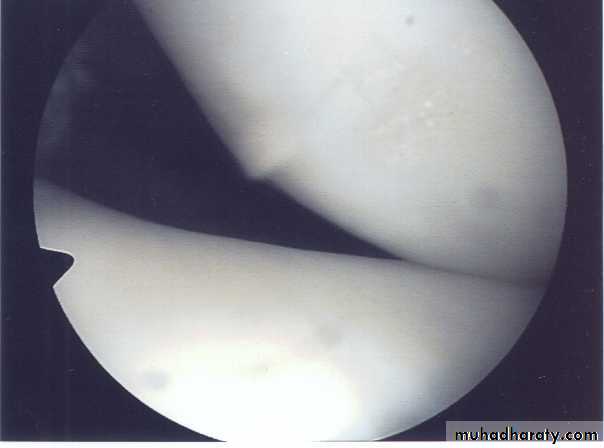

• Arthroscopy; it’s the best to give direct visualization of the inside of the joint to prove the diagnosis & exclude other possible injuries.

Arthroscopy can prove the diagnosis & show the site & type of the tear. Conservative treatment is only indicated for peripheral tears where the vascular meniscus may heal if the knee is rested for 3-4 weeks in POP or if the meniscus is sutured.Otherwise operative treatment is always indicated by arthroscopy, the aim is to excise the torn part of the meniscus only & leave the remaining intact part to avoid later degenerative changes of the knee.

Arthroscopy: can prove diagnosis & sometimes used for treatment.

Chronic swelling, givingway, locking & pain are common.X-ray: it may show loose bodies.Arthroscopy: can prove the diagnosis (snowstorm appearance).